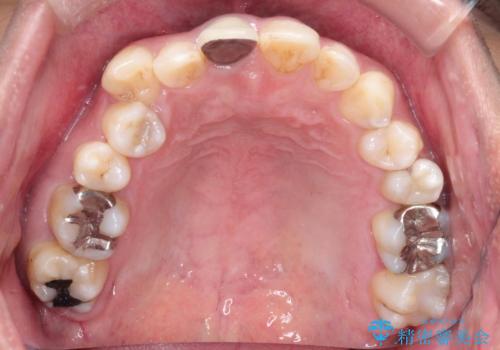

【インビザライン】八重歯と歯のでこぼこが気になる!

- 「八重歯と歯のでこぼこを治したい」を主訴に来院された患者様です。

歯は抜かずに奥歯の遠心移動とIPRで八重歯とでこぼこを改善しました。

左上3番は保険治療(CR)の劣化による二次カリエスになっていますので、後日治療予定です。